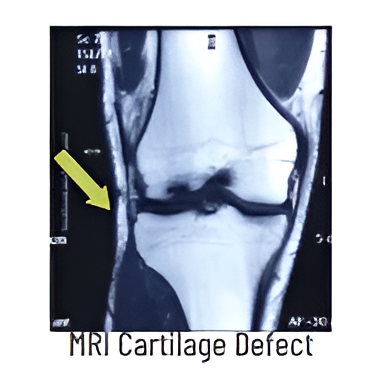

Cartilage injury

Knee joint surface is covered by Hyaline Cartilage, which is responsible for smooth and frictionless movements. When injured it does not heal due to lack of blood supply. Repair techniques include – MICROFRACTURE (bone marrow stimulation with drilling) suitable for small lesions, OATS, in which cylindrical plugs of cartilage from non-weight bearing areas are transferred to thedefects and Cell based techniques in which concentrated stem cells from bone marrow (BMAC) or patient’s own cartilage cells (ACI) grown in a lab are used to fill the defect.

Focal cartilage defects, are treated with variety of techniques. Small defects are treated with Microfracture- marrow stimulating techniques. Large defects are treated with cartilage plug transfers (OATS, mosaicplasty), ACI (cartilage cell culture & repair) and single stage BMA cartilage. Diffuse cartilage wear may need HTO in early stage or TKR in advanced stage